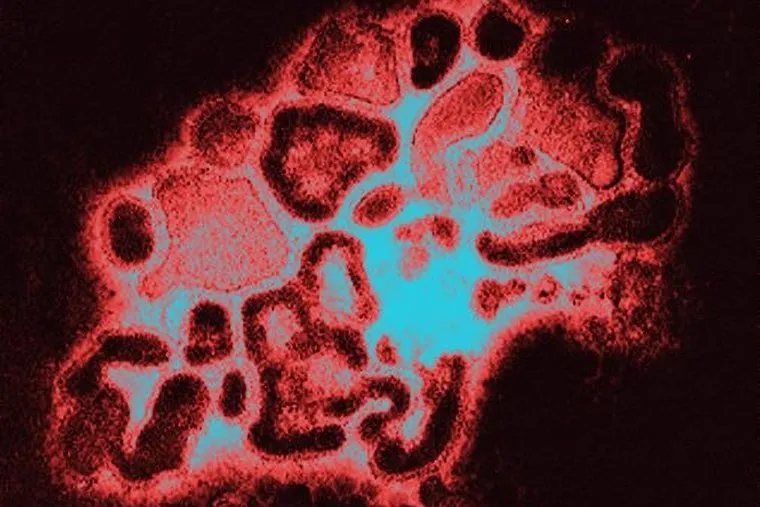

За считанные часы после заражения вирус приводит к глубоким поражениям слизистой оболочки дыхательных путей

Фото: Фото: Custom Medical Stock Photo/Globallookpress